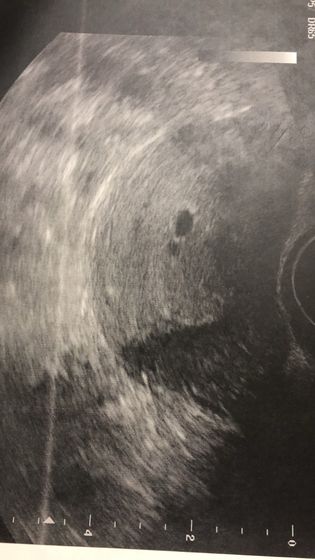

Дождалась УЗИ. Плодное яйцо в матке) но эмбриона не видно...:( рядом что то ещё. Либо включение матки, либо второй ??